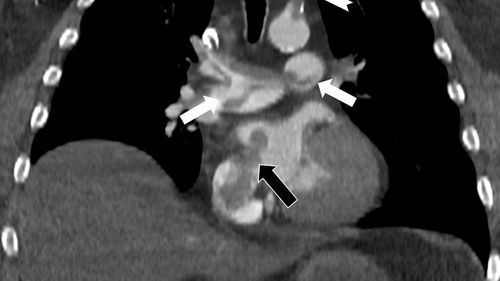

Prof. Dr. Nevzat Karabulut’un Radiology’de yayımlanan çalışması, kalpteki gizli deliklerin pıhtının sağdan sola geçerek yaşamı tehdit eden paradoks emboliye neden olabileceğini gösterdi.

Prof. Dr. Nevzat Karabulut’tan kalpteki gizli deliklerin paradoks emboli riski üzerine çalışmasıÇalışmanın özeti ve yayımlandığı mecraRadyoloji Uzmanı Prof. Dr. Nevzat Karabulut, Özel Denizli Tekden Hastanesi’nde görev yaptığı dönemdeki deneyimini de taşıyan araştırmasında, kalpteki gizli deliklerin hayatı tehdit eden paradoks emboliye…